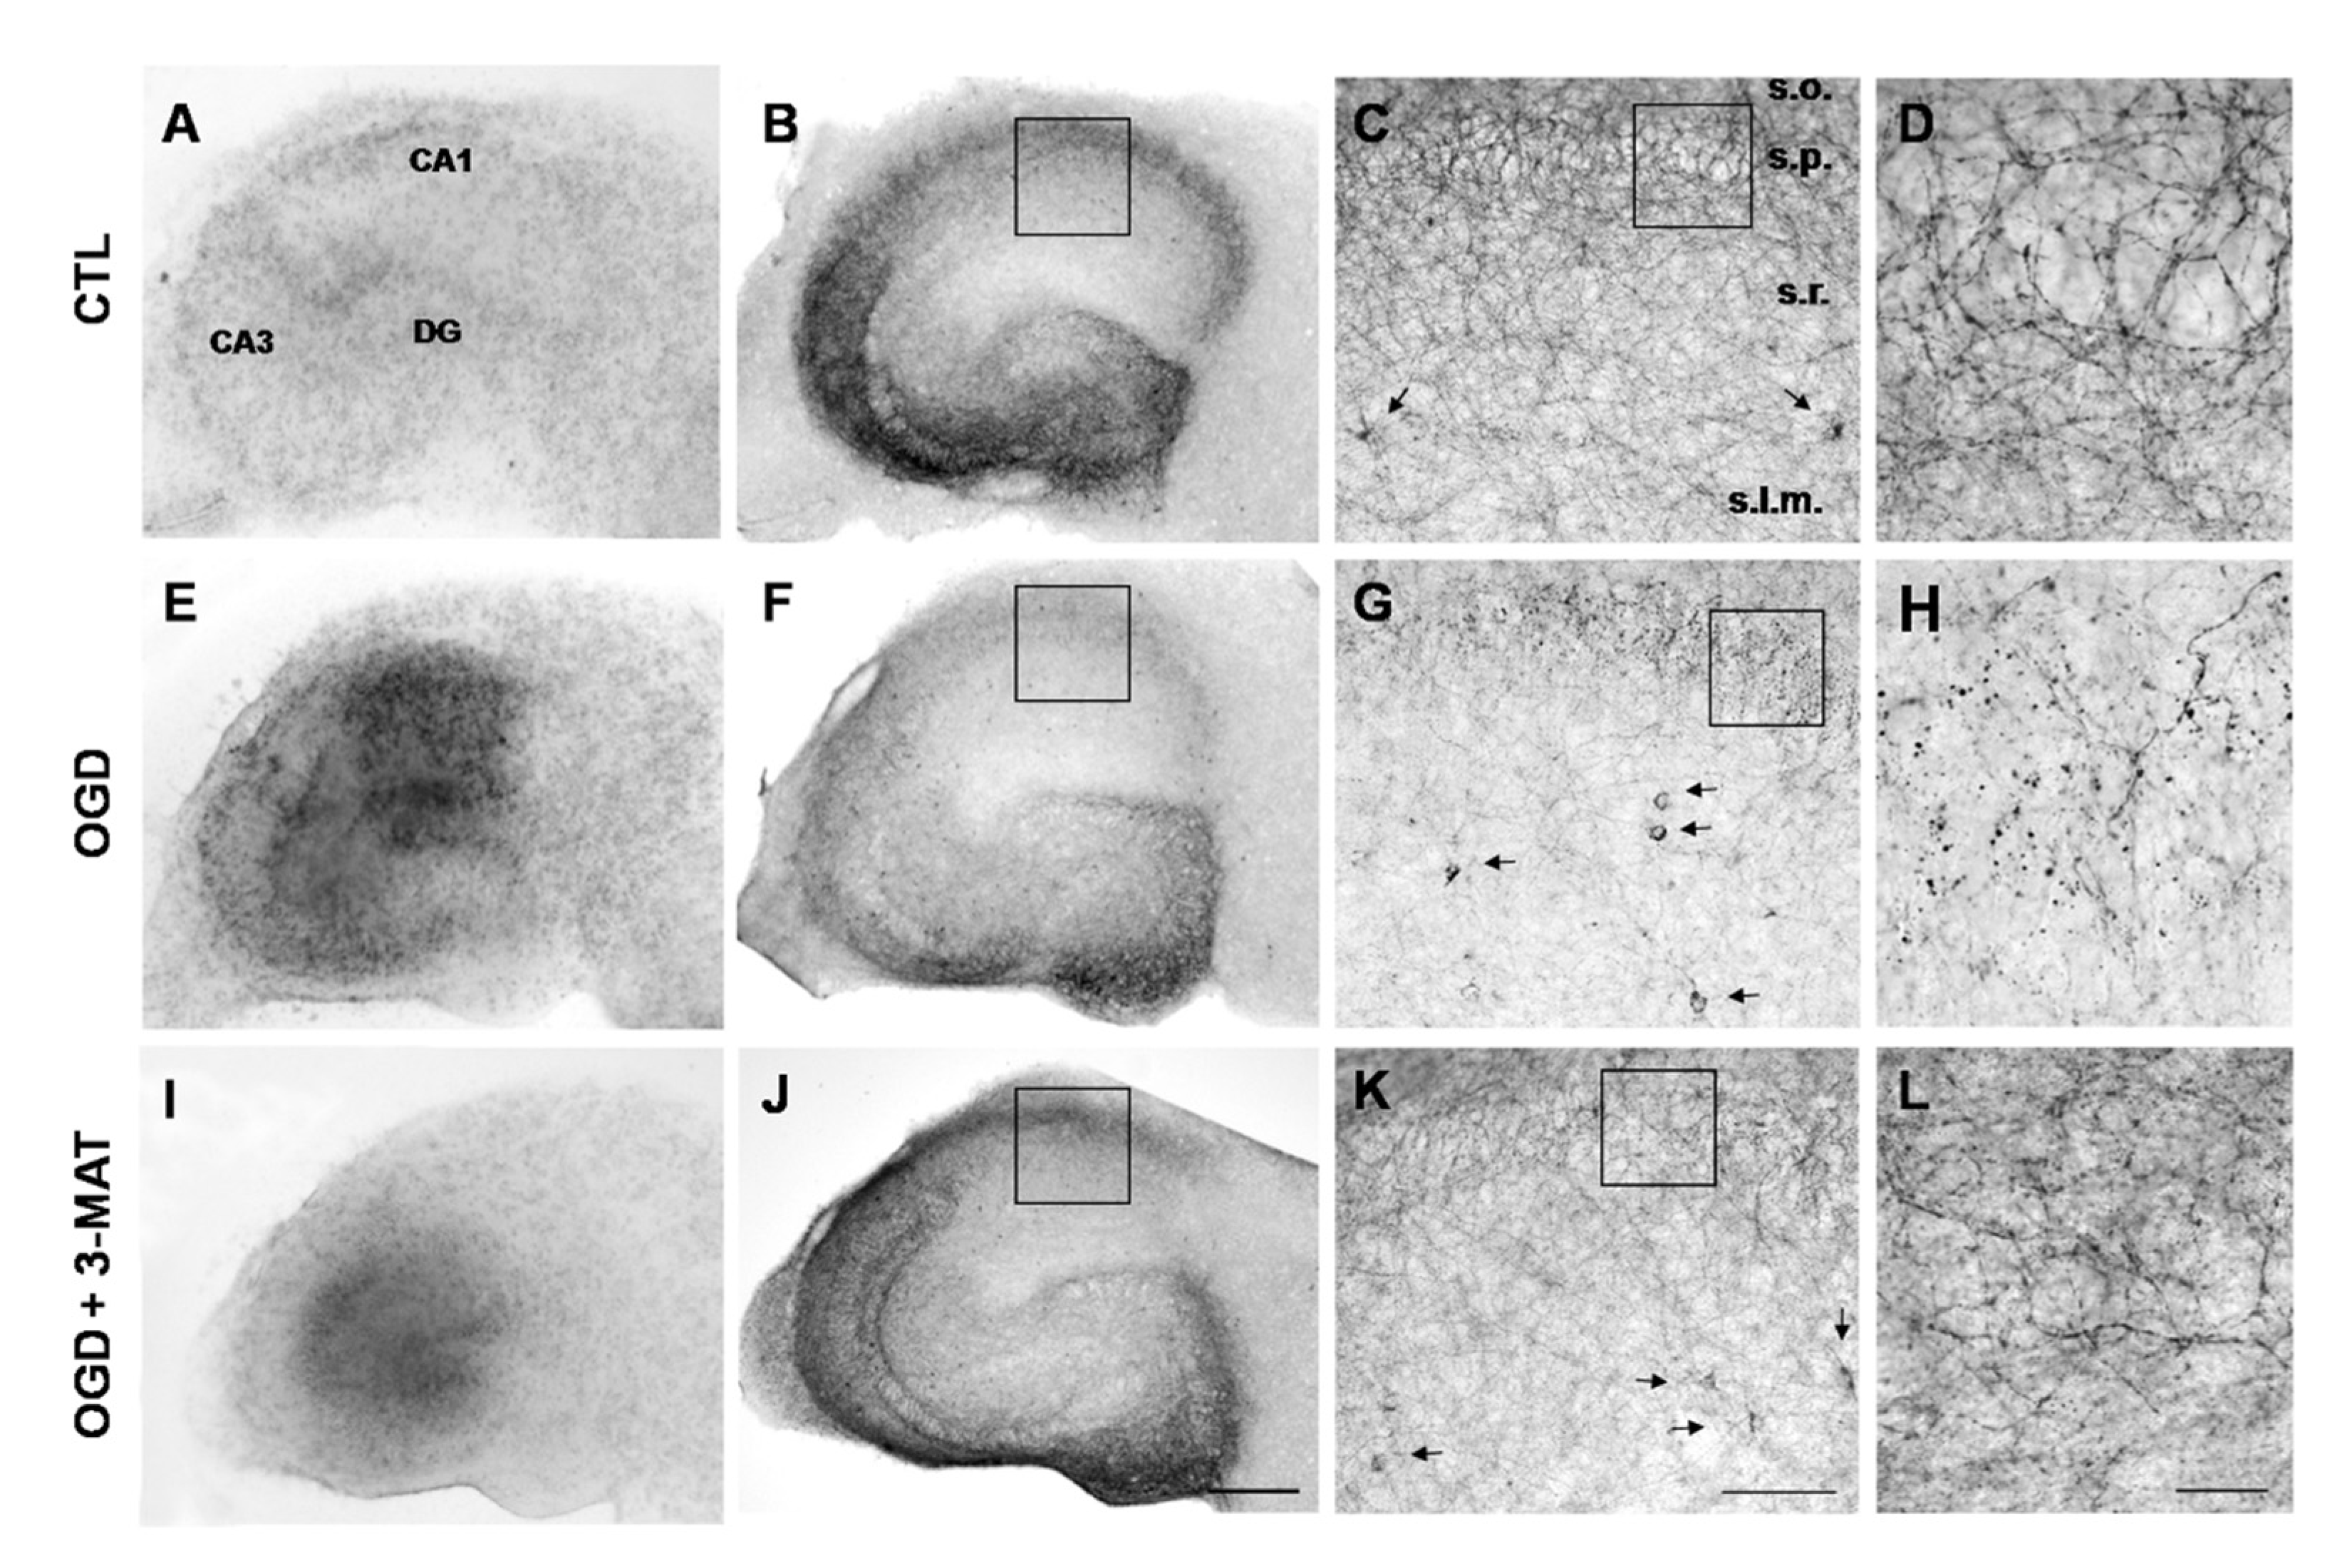

3.4. The Disruption of Cb1-Like Immunoreactivity in Organotypic Hippocampal Slices Exposed to OGD Is Reduced by mGlu1 Receptor Antagonists